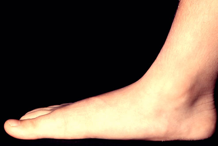

Πλατυποδία

Η πλατυποδία χαρακτηρίζεται από μη σωστή κλίση της καμάρας του πέλματος, με αποτέλεσμα όλο το πέλμα να ακουμπάει στο έδαφος. Μπορεί να έχει κληρονομηθεί, να προκληθεί από τραυματισμό ή από κάποια ασθένεια, όπως είναι η ρευματοειδής αρθρίτιδα. Τα ενοχλητικά συμπτώματα της πλατυποδίας είναι σπάνια, αλλά η πρόσληψη βάρους, τα παπούτσια με κακή εφαρμογή ή η ορθοστασία, μπορεί να προκαλέσουν πόνο σε άτομα με πλατυποδία. Η θεραπεία περιλαμβάνει ειδικές ασκήσεις για την ενδυνάμωση του πέλματος και ειδικά παπούτσια για σωστή υποστήριξη της καμάρας.